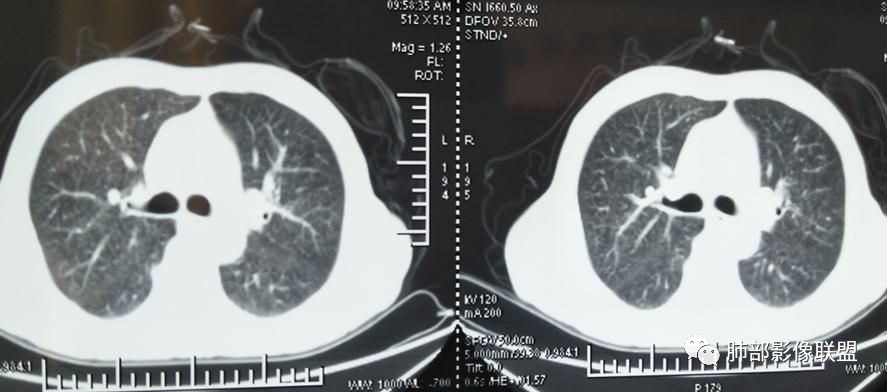

2019年9月12日CT(外院片,手机拍摄)

2019-10-20复查CT如下:

两肺弥漫性粟粒样结节伴左上肺小结节,呈三均匀分布,有结核的临床表现,支持血性播散性肺结核。

大小、分布均匀,边缘清楚

细小结节,弥漫,撒米粒样——血道来源

血道来源的病灶,均匀、细微,而且部分有分支状,都符合粟粒型肺结核

急性血行播散型肺结核  两肺广泛分布粟粒大小的结节状密度增高影,具有大小均匀、分布均匀、密度均匀的典型“三均匀”特征,注意急性血播病灶非常小,一般粟粒影直径1~2mm。

病灶密集者出现肺外围血管影不清或减少。

发热初期肺部可缺乏典型影像学改变,1到2周后出现的广泛粟粒结节对诊断具有高度提示作用!